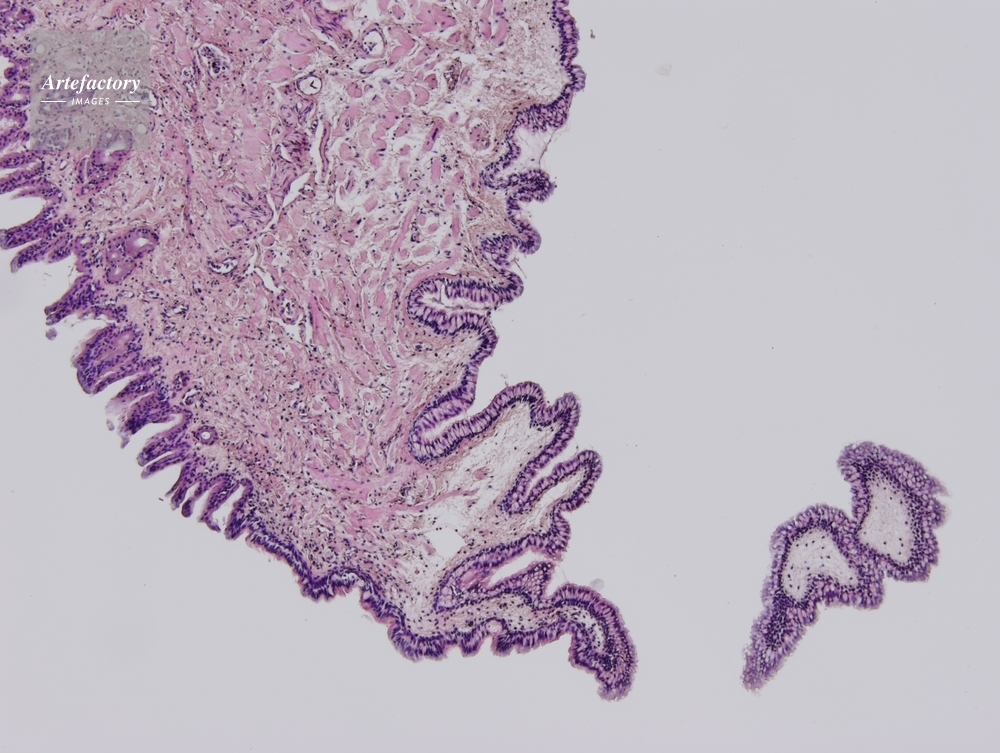

| 作品タイトル | ウシガエル 舌 | モデルリリース | なし | |

| 作家 | OLYMPUS CORPORATION Technolab | プロパティリリース | なし | |

| 撮影年月日 | 2007/4/20 | データサイズ | 4.6MByte | |